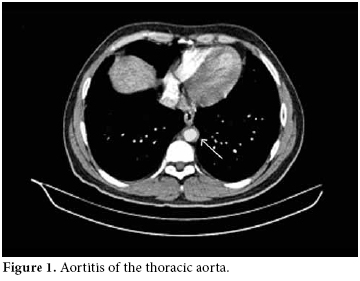

A 28-year-old male patient was admitted to our hospital with complaints of severe abdominal pain and nausea which had started six weeks previously. There were painful, maculopapular lesions that responded well to a topical steroid in both of the palms. The patient had also been suffering from photosensitivity for the last eight months. He had been diagnosed with type 1 diabetes mellitus (DM) and prothrombin 20210a gene mutation during the last 12 years and he had also a history of deep vein thrombosis (DVT) in 2002 and pulmonary thrombo embolism (PTE) in 2006. His mother also had a history of prothrombin 20210a gene mutation and type I DM. He was being treated with a daily dose of glargine insulin and warfarin. His physical examination at the time of admission revealed hypertension (170/100 mmHg), maculopapular lesions on both palms, hepatosplenomegaly, and abdominal tenderness. The laboratory examination was as follows: white blood cells (WBC) counts 15000/mm3, hemoglobin 16.3 gr/dl, platelets 92 000/mm3, blood urea nitrogen (BUN) 20 mg/dl, creatinine 1.46 mg/dl, erythrocyte sedimentation rate (ESR) 40 mm/h, C-reactive protein (CRP) 8.8 mg/dl (0-0.8), and fibrinogen 712 mg/dl (219-403). A urinalysis presented the following results: +++protein, +++blood, no casts, and microprotein in 24 h urine 900 mg/day (0-80). The serologic tests were the followiong: anti-nuclear antibodies 1/320 (homogeneous pattern), anti-double-stranded deoxyribonucleic acid (anti‐dsDNA) 1.7 (0-1.1), rheumatoid factor 22.0 IU/mL (0-15), anti-cardiolipin IgG>300 GPL/mL (0-15), and anti-phospholipid IgG 232 GPL/mL (0-15). A chest X-ray showed minimal pleural effusion and the electrocardiography ECG was normal. There was no thrombus and no vegetation in the transesophageal echocardiography (TEEC). For further evaluation of the thrombocytopenia, bone marrow aspiration and a biopsy were performed, but there were no pathological findings to explain the situation. Also, a skin biopsy from the palms was done to search for the etiology, but this also yielded no clues. Angiography with abdominal computed tomography revealed a thickening of the wall of the thoracic and abdominal aorta and an increased density of the surrounding fat tissues at the level of bifurcation. These were compatible with the diagnosis of vasculitis and retroperitoneal fibrosis (figures 1 and 2).

Another important argument in this case is determining whether the aortitis was secondary to retroperitoneal fibrosis or not. The main evidence that these two are present together is that the aortitis is located in the thoracic part of the aorta, but the retroperitoneal fibrosis is located in the abdominal region.